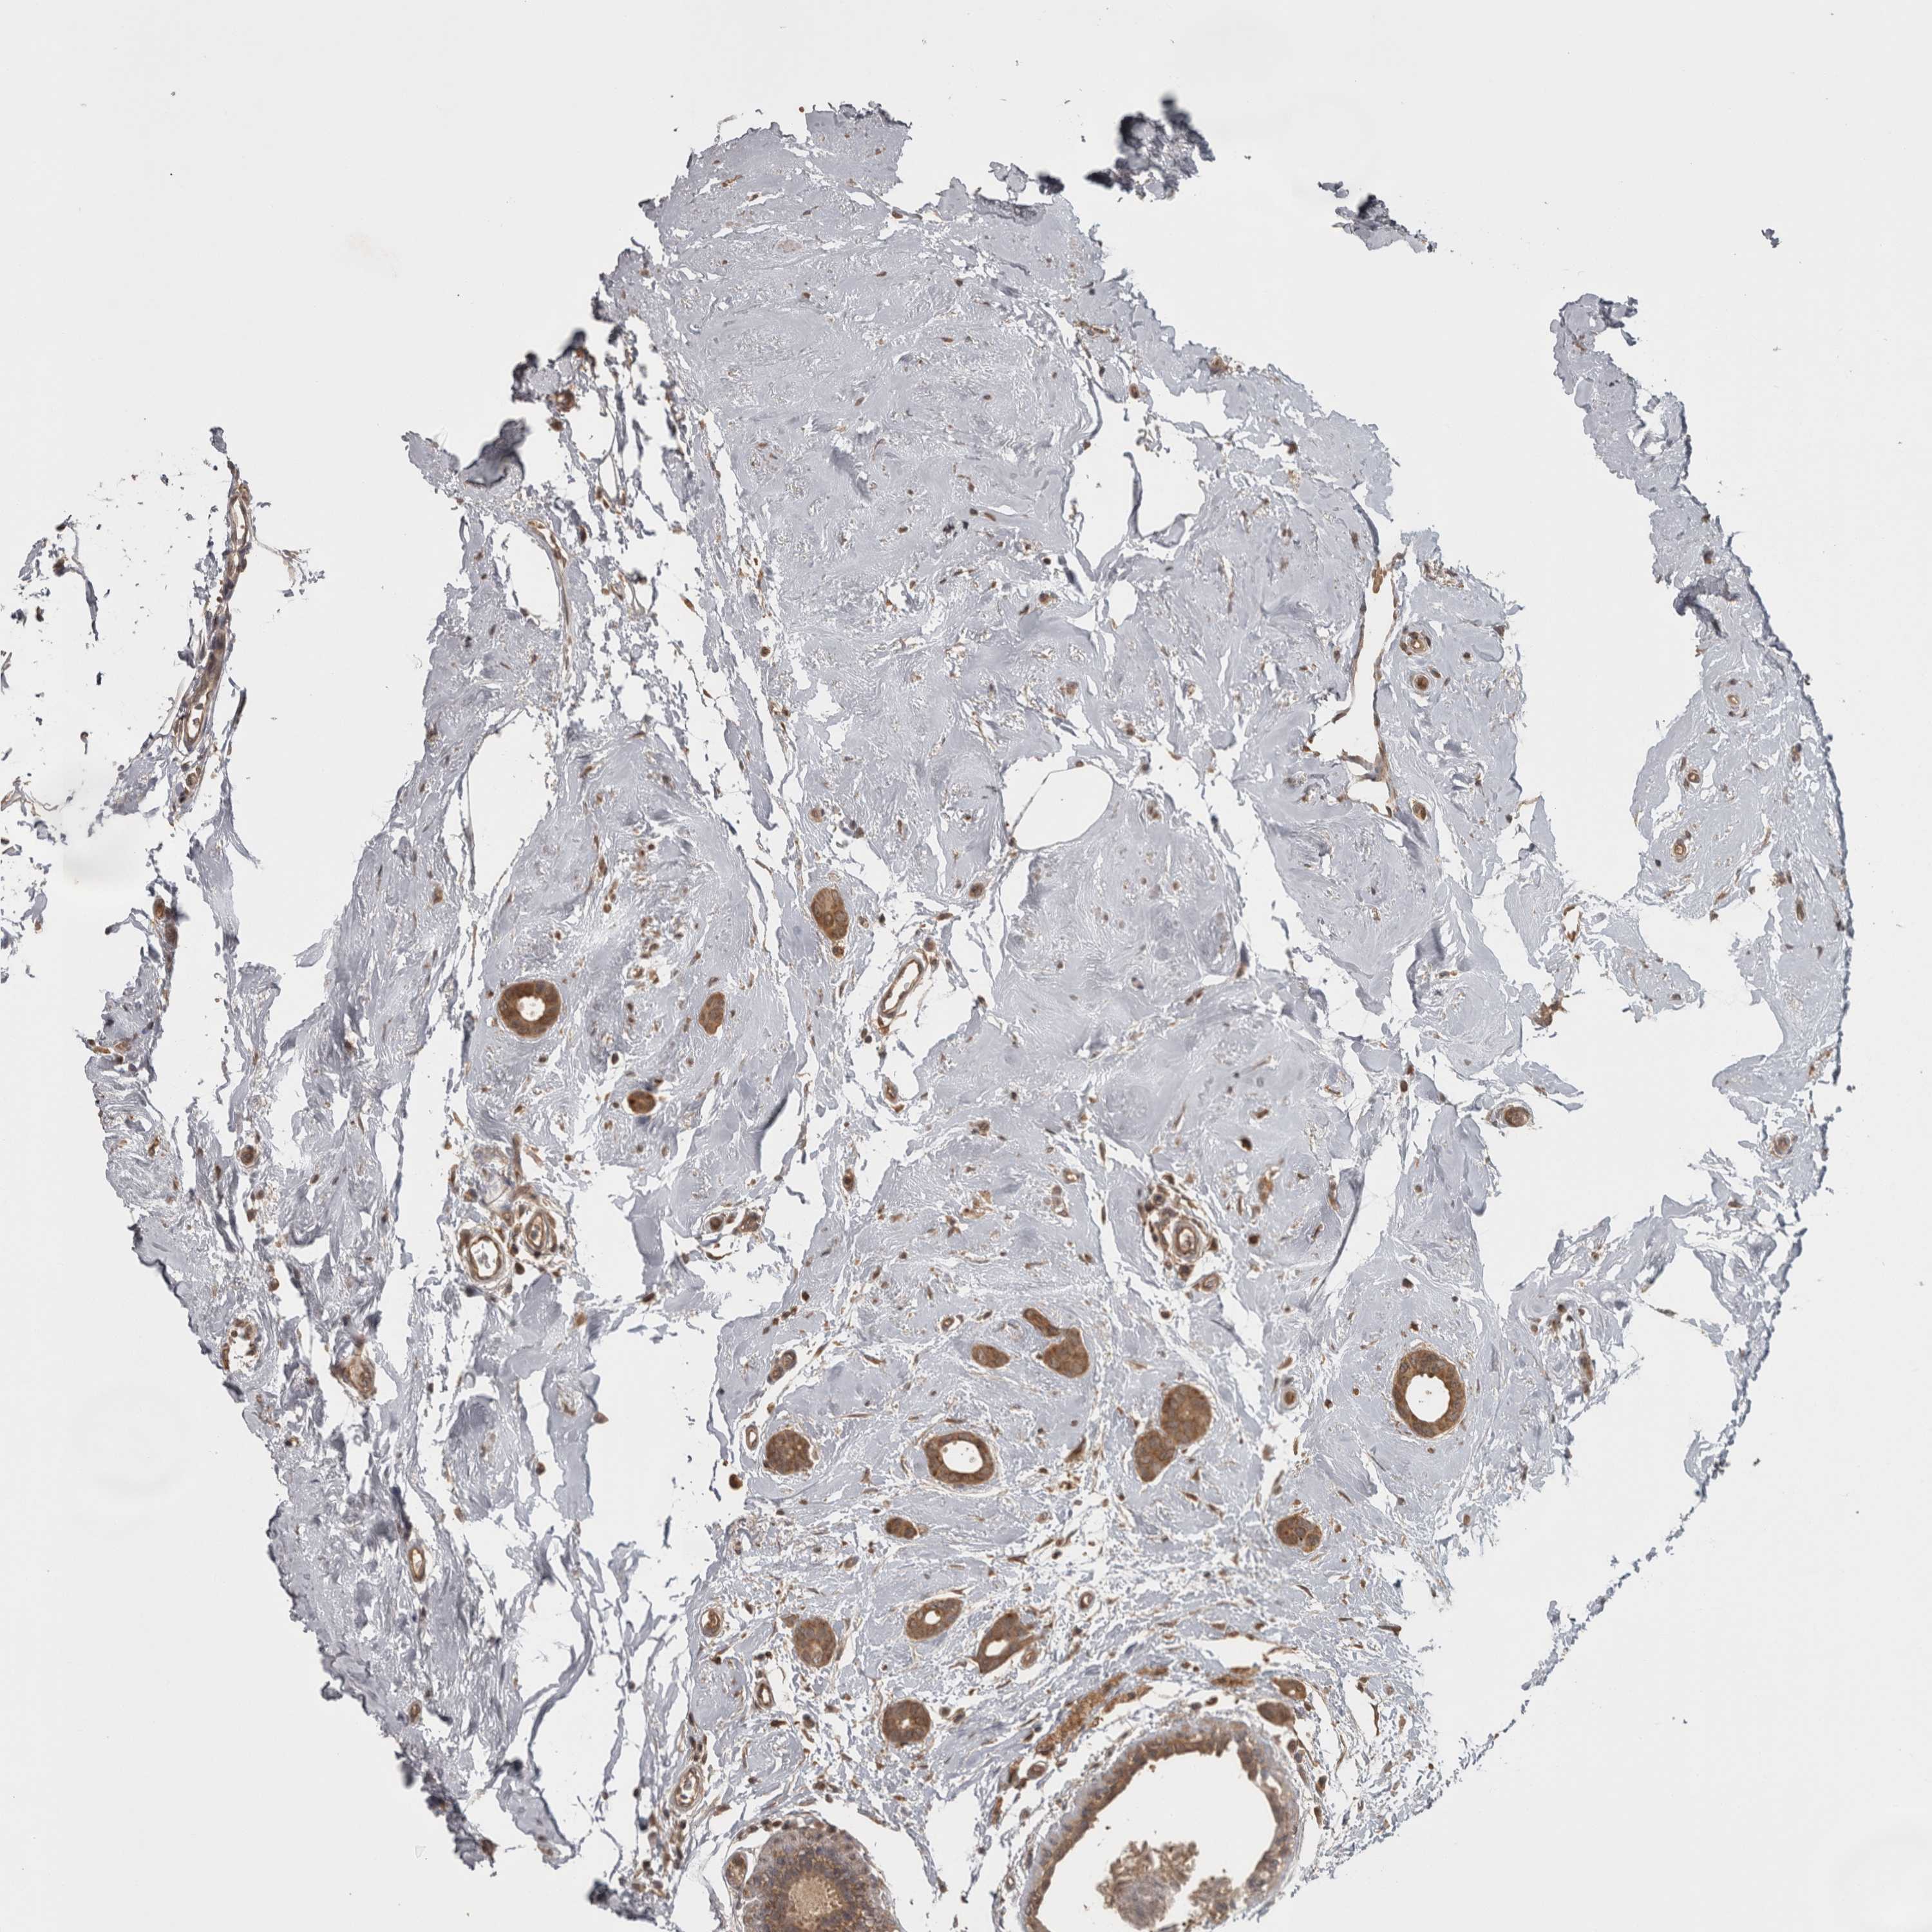

CANCER BREAST CANCER Show tissue menu

BRCA TCGA BRCA VALIDATION PROTEIN EXPRESSION